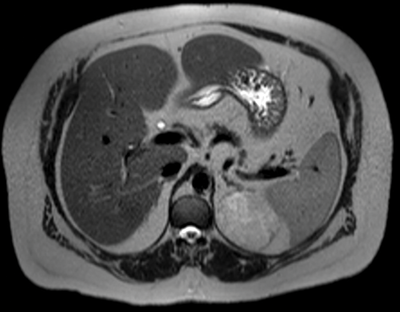

Assessment of the incidental adrenal lesion

Introduction The adrenal glands are seen on CT or MRI surrounded by fat in the peri-renal space. The right adrenal gland lies medial to the right lobe of the liver, lateral to the right crus of the diaphragm and superior...